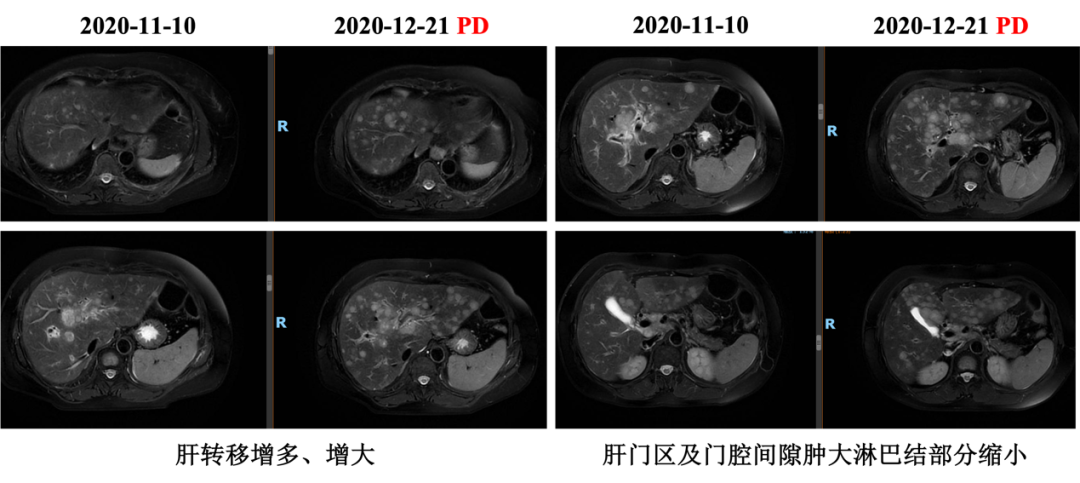

▌五线治疗:

自2020-11-10行白蛋白紫杉醇+伊尼妥单抗治疗2周期,具体:伊尼妥单抗8mg/kg 首剂,6mg/kg 后续d1+白蛋白紫杉醇125mg/m2 200mg d1、d8,Q21d。2周期后肝转移增多、增大,肝门区及门腔间隙肿大淋巴结部分缩小,综合评效PD,PFS为1.5月。

图6. 五线治疗